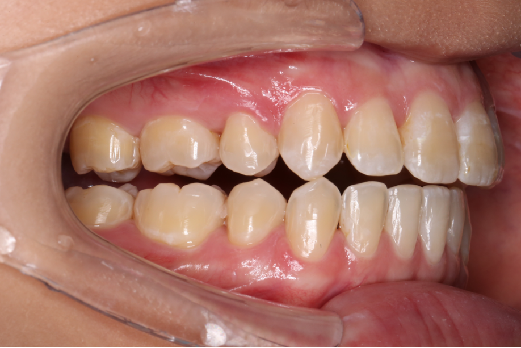

2018.11.14  术后磨牙尖牙I类关系,中线齐,覆合,覆盖正常

2018.11.14  术后侧面改善明显,露龈笑改善明显,笑弧笑线协调,颏部肌肉紧张度明显改善

宏观评价:面部对称,面下三分一比例协调,上下唇凸度正常,上颌牙列内收转矩控制良好,下颌后缩改善,颏唇沟变得更加柔和,术后达到基本直面型。

迷你观评价:上下牙齿中线与面中线对齐,笑弧协调,微笑时牙龈暴露量正常,微笑时横向正常,左右唇基本对称。

微观评价:牙齿整齐,咬合关系良好,上下前牙转矩及突度控制良好,磨牙关系I类,尖窝咬合关系良好,OB,OJ正常。